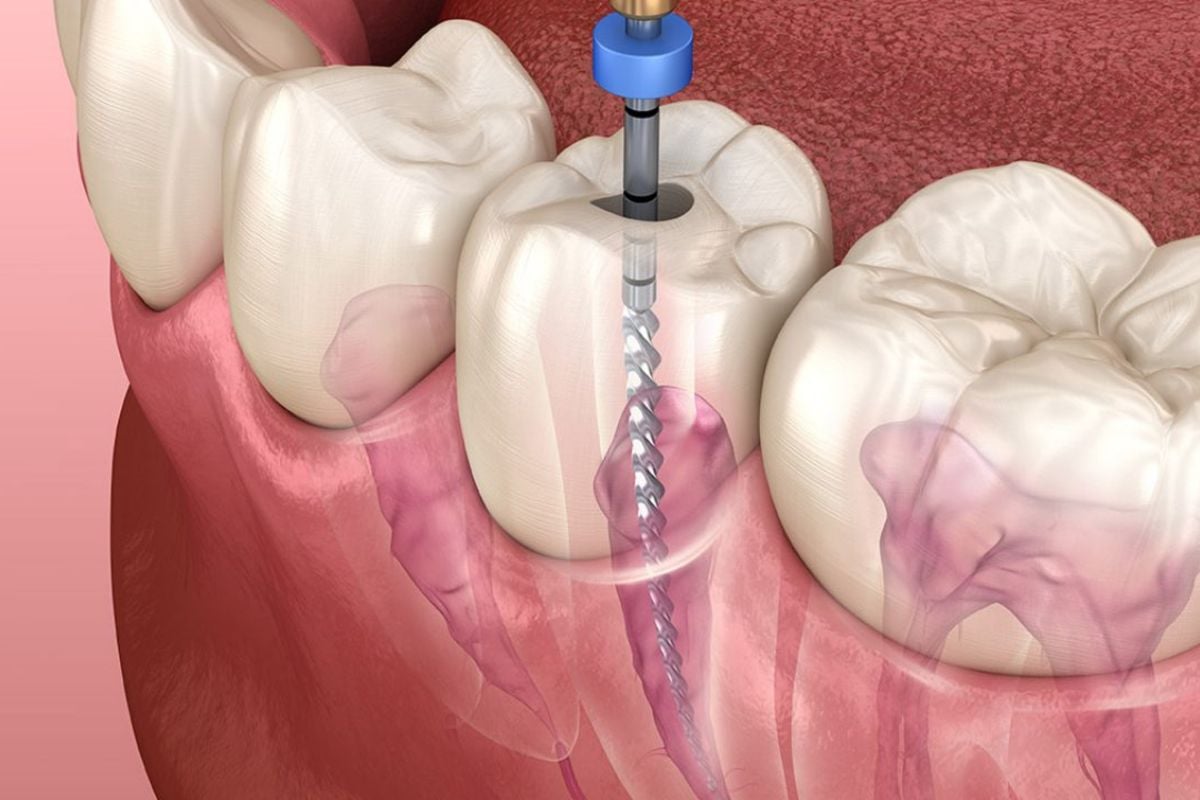

هذه الزرعات طفرة في طب الأسنان الحديث، وهي عبارة عن جذور اصطناعية مصنوعة بدقة في المختبرات السويسرية ليتم غرسها في عظم الفك كبديل دائم للأسنان المفقودة، تعتمد فكرتها على تقنية الالتحام العظمي التي تسمح للزرعة بالاندماج مع أنسجة الجسم الطبيعية لتصبح جزءا لا يتجزأ من الفك، وما يميزها في عيادات عناية هو جودتها الأصلية التي تضمن عدم تآكلها أو تغير لون اللثة المحيطة بها، حيث تخضع لرقابة صارمة تضمن خلوها من الشوائب، مما يوفر للمريض أساسا قويا ومتيناً لتركيب التيجان والجسور السنية بمظهر طبيعي وجذاب تماماً يدوم لسنوات طويلة.

الزرعات السويسرية المرجع العالمي الأول للجودة بفضل الأبحاث السريرية المطولة التي جعلتها تحقق أعلى نسب نجاح في العالم، وفي عيادات عناية نختار لك الأفضل دائما لضمان راحتك، وتعتمد هذه الزرعات على تقنيات معالجة الأسطح المبتكرة التي تسرع من عملية الاندماج العظمي حتى في الحالات التي تعاني من نقص في كثافة العظام، مما يقلل فترة الانتظار بين الزراعة والتركيب النهائي بشكل ملحوظ، الاختيار الصحيح للزرعة المناسبة يتم بدقة بعد دراسة حالة المريض وتصوير الفك بالأشعة ثلاثية الأبعاد لتحديد العمق والزاوية المثالية للغرس، والحصول على النوع الأصلي يضمن لك تفادي المضاعفات الشائعة مثل الالتهابات أو رفض الجسم للزرعة، حيث توفر الصناعة السويسرية متانة استثنائية وقدرة عالية على تحمل ضغوط المضغ اليومية القوية.

- وضع خطة علاجية مفصلة تشمل عدد الزرعات المطلوبة وتحديد الزوايا والعمق الأمثل لغرسها في نسيج الفك.